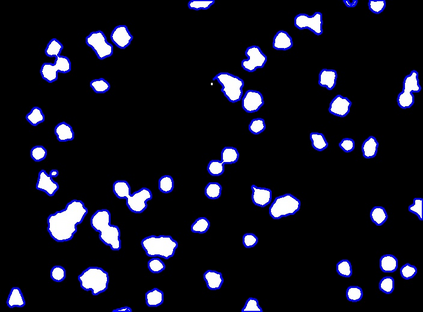

Bright-field microscopy, a cost-effective solution for live-cell culture, is often the only resource available, along with standard CPUs, for many low-budget labs. The inherent challenges of bright-field images -- their noisiness, low contrast, and dynamic morphology -- coupled with a lack of GPU resources and complex software interfaces, hinder the desired research output. This article presents a novel microscopy image analysis framework designed for low-budget labs equipped with a standard CPU desktop. The Python-based program enables cytometric analysis of live, unstained cells in culture through an advanced computer vision and machine learning pipeline. Crucially, the framework operates on label-free data, requiring no manually annotated training data or training phase. It is accessible via a user-friendly, cross-platform GUI that requires no programming skills, while also providing a scripting interface for programmatic control and integration by developers. The end-to-end workflow performs semantic and instance segmentation, feature extraction, analysis, evaluation, and automated report generation. Its modular architecture supports easy maintenance and flexible integration while supporting both single-image and batch processing. Validated on several unstained cell types from the public dataset of livecells, the framework demonstrates superior accuracy and reproducibility compared to contemporary tools like Cellpose and StarDist. Its competitive segmentation speed on a CPU-based platform highlights its significant potential for basic research and clinical applications -- particularly in cell transplantation for personalised medicine and muscle regeneration therapies. The access to the application is available for reproducibility